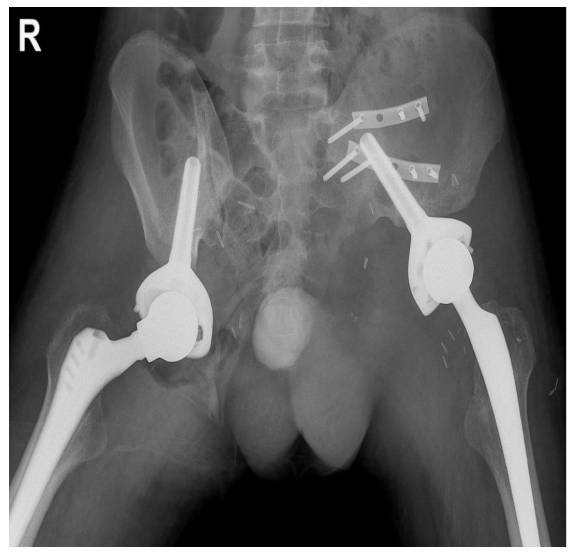

- The patient underwent extensive resection (Type II+III hemipelvectomy) followed by reconstruction (Lumic).

- At the 6th month of follow-up, metastases were detected in the right acetabulum and pubic arm of the patient. Since no additional metastases were detected in subsequent scans, the same surgical procedure was performed on the right side as well.

Postoperative: X-ray shows sacroiliac fixation after resection (due to instability) and reconstruction with Lumic prosthesis.

Postoperative: The X-ray shows reconstruction with Lumic prosthesis after bilateral internal hemipelvectomy.